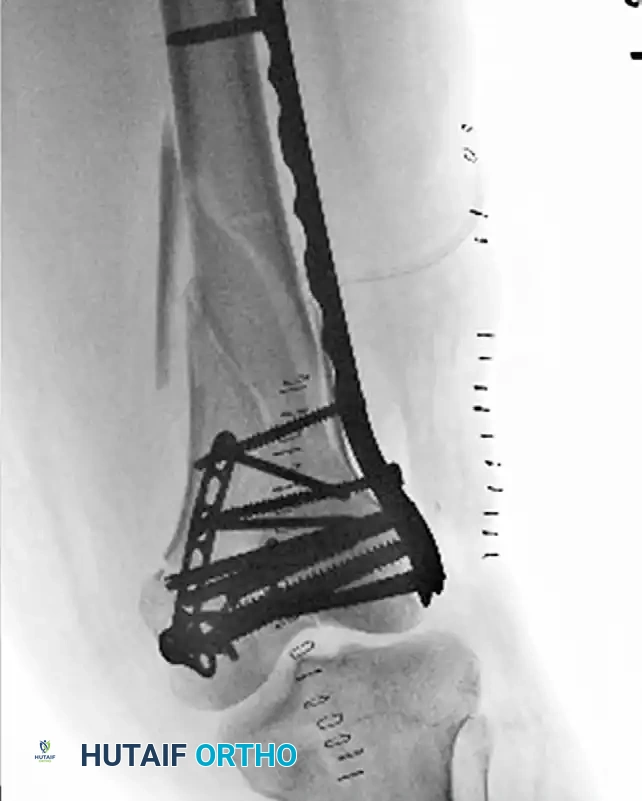

Postoperative radiograph demonstrating small fragment fixation of the medial femoral condyle through a subvastus approach, acting as a biomechanical adjuvant to the more typical lateral-based fixation construct.